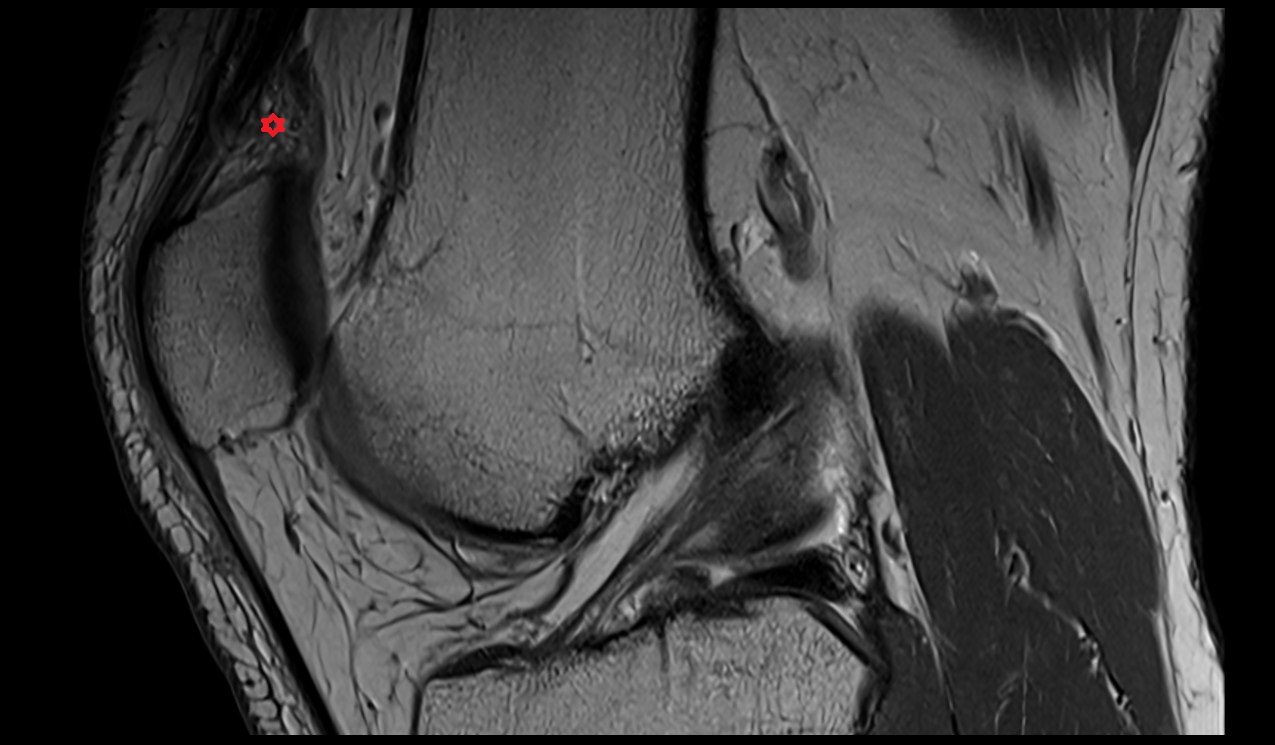

- Anterior cruciate ligament

- Posterior cruciate ligament

- Patellar tendon (patellar ligament)

- Infrapatellar fat pad

- Suprapatellar fat pad

- Prefemoral fat pad